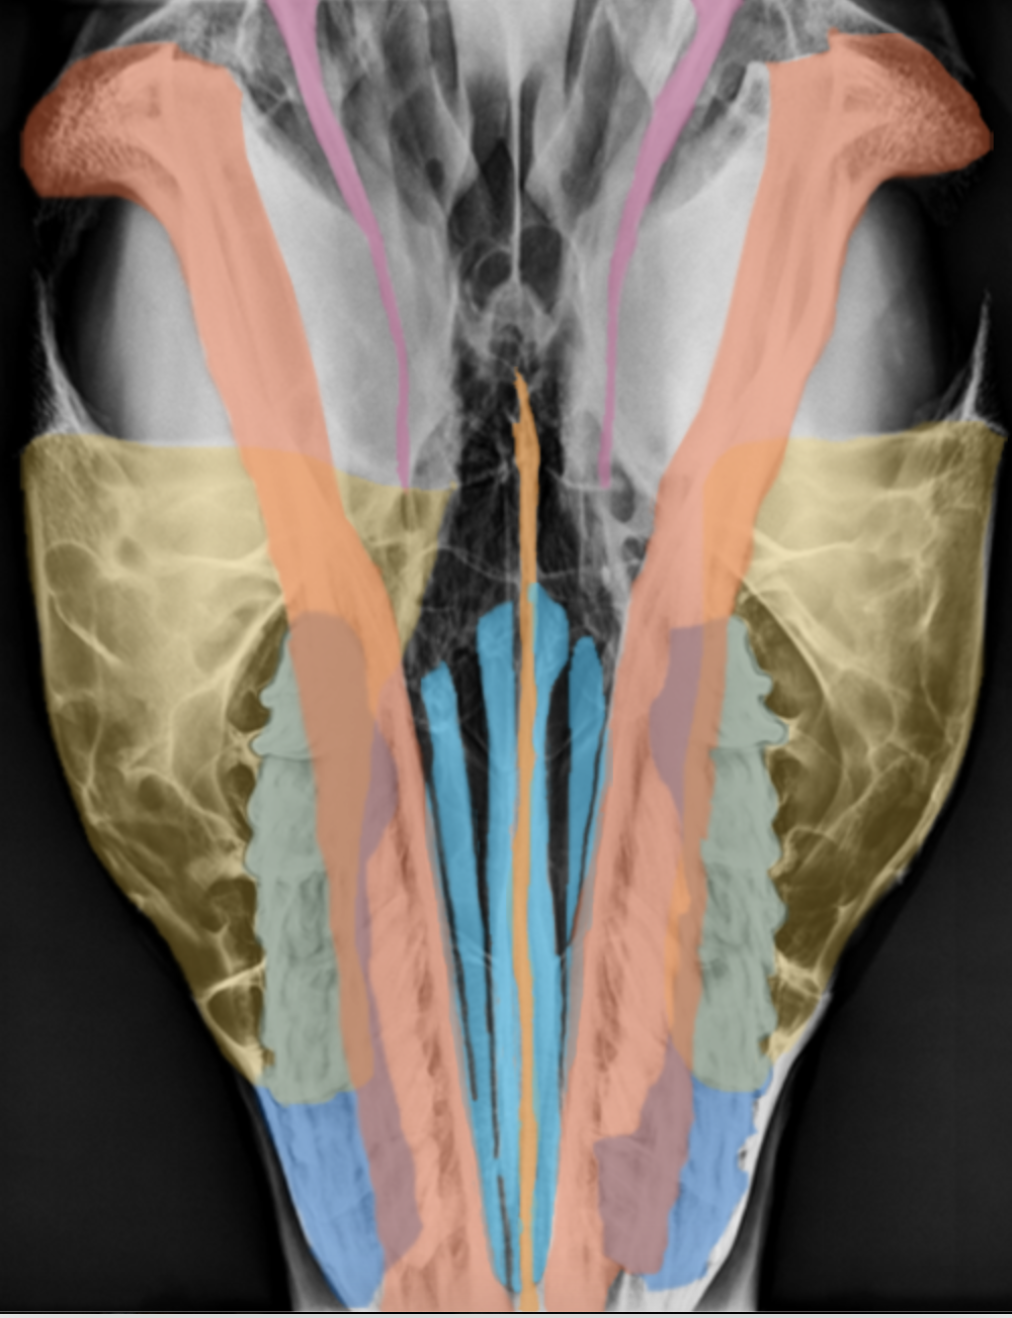

dorsoventral equine skull

red: mandibles

blue: nasal turbinates (conchi)

orange: vomer

yellow: maxillary sinus

pink: styelohyoid bones

dark blue: maxillary teeth